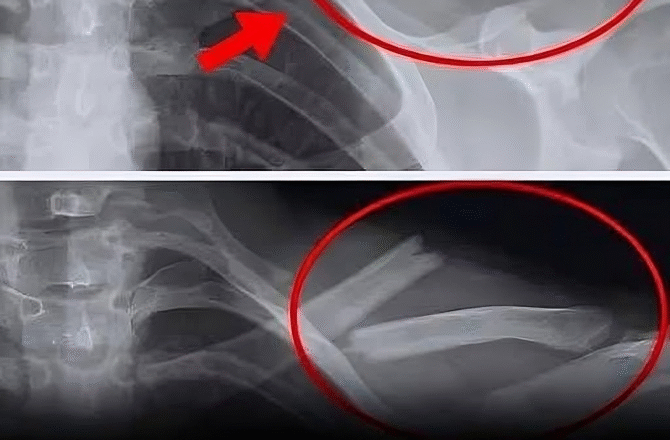

Слабкі кістки / Остеопороз

Вживання газованих напоїв збільшує ризик розвитку остеопорозу через дію фосфорної кислоти, яка перешкоджає правильному засвоєнню кальцію, послаблюючи кістки.

Дослідження, проведене Університетом Тафтса, показало, що жінки, які пили газовану воду тричі на тиждень, мали в середньому на 4% більшу втрату кісткової маси (у таких областях, як стегна), ніж група жінок, які вживали інші види напоїв.